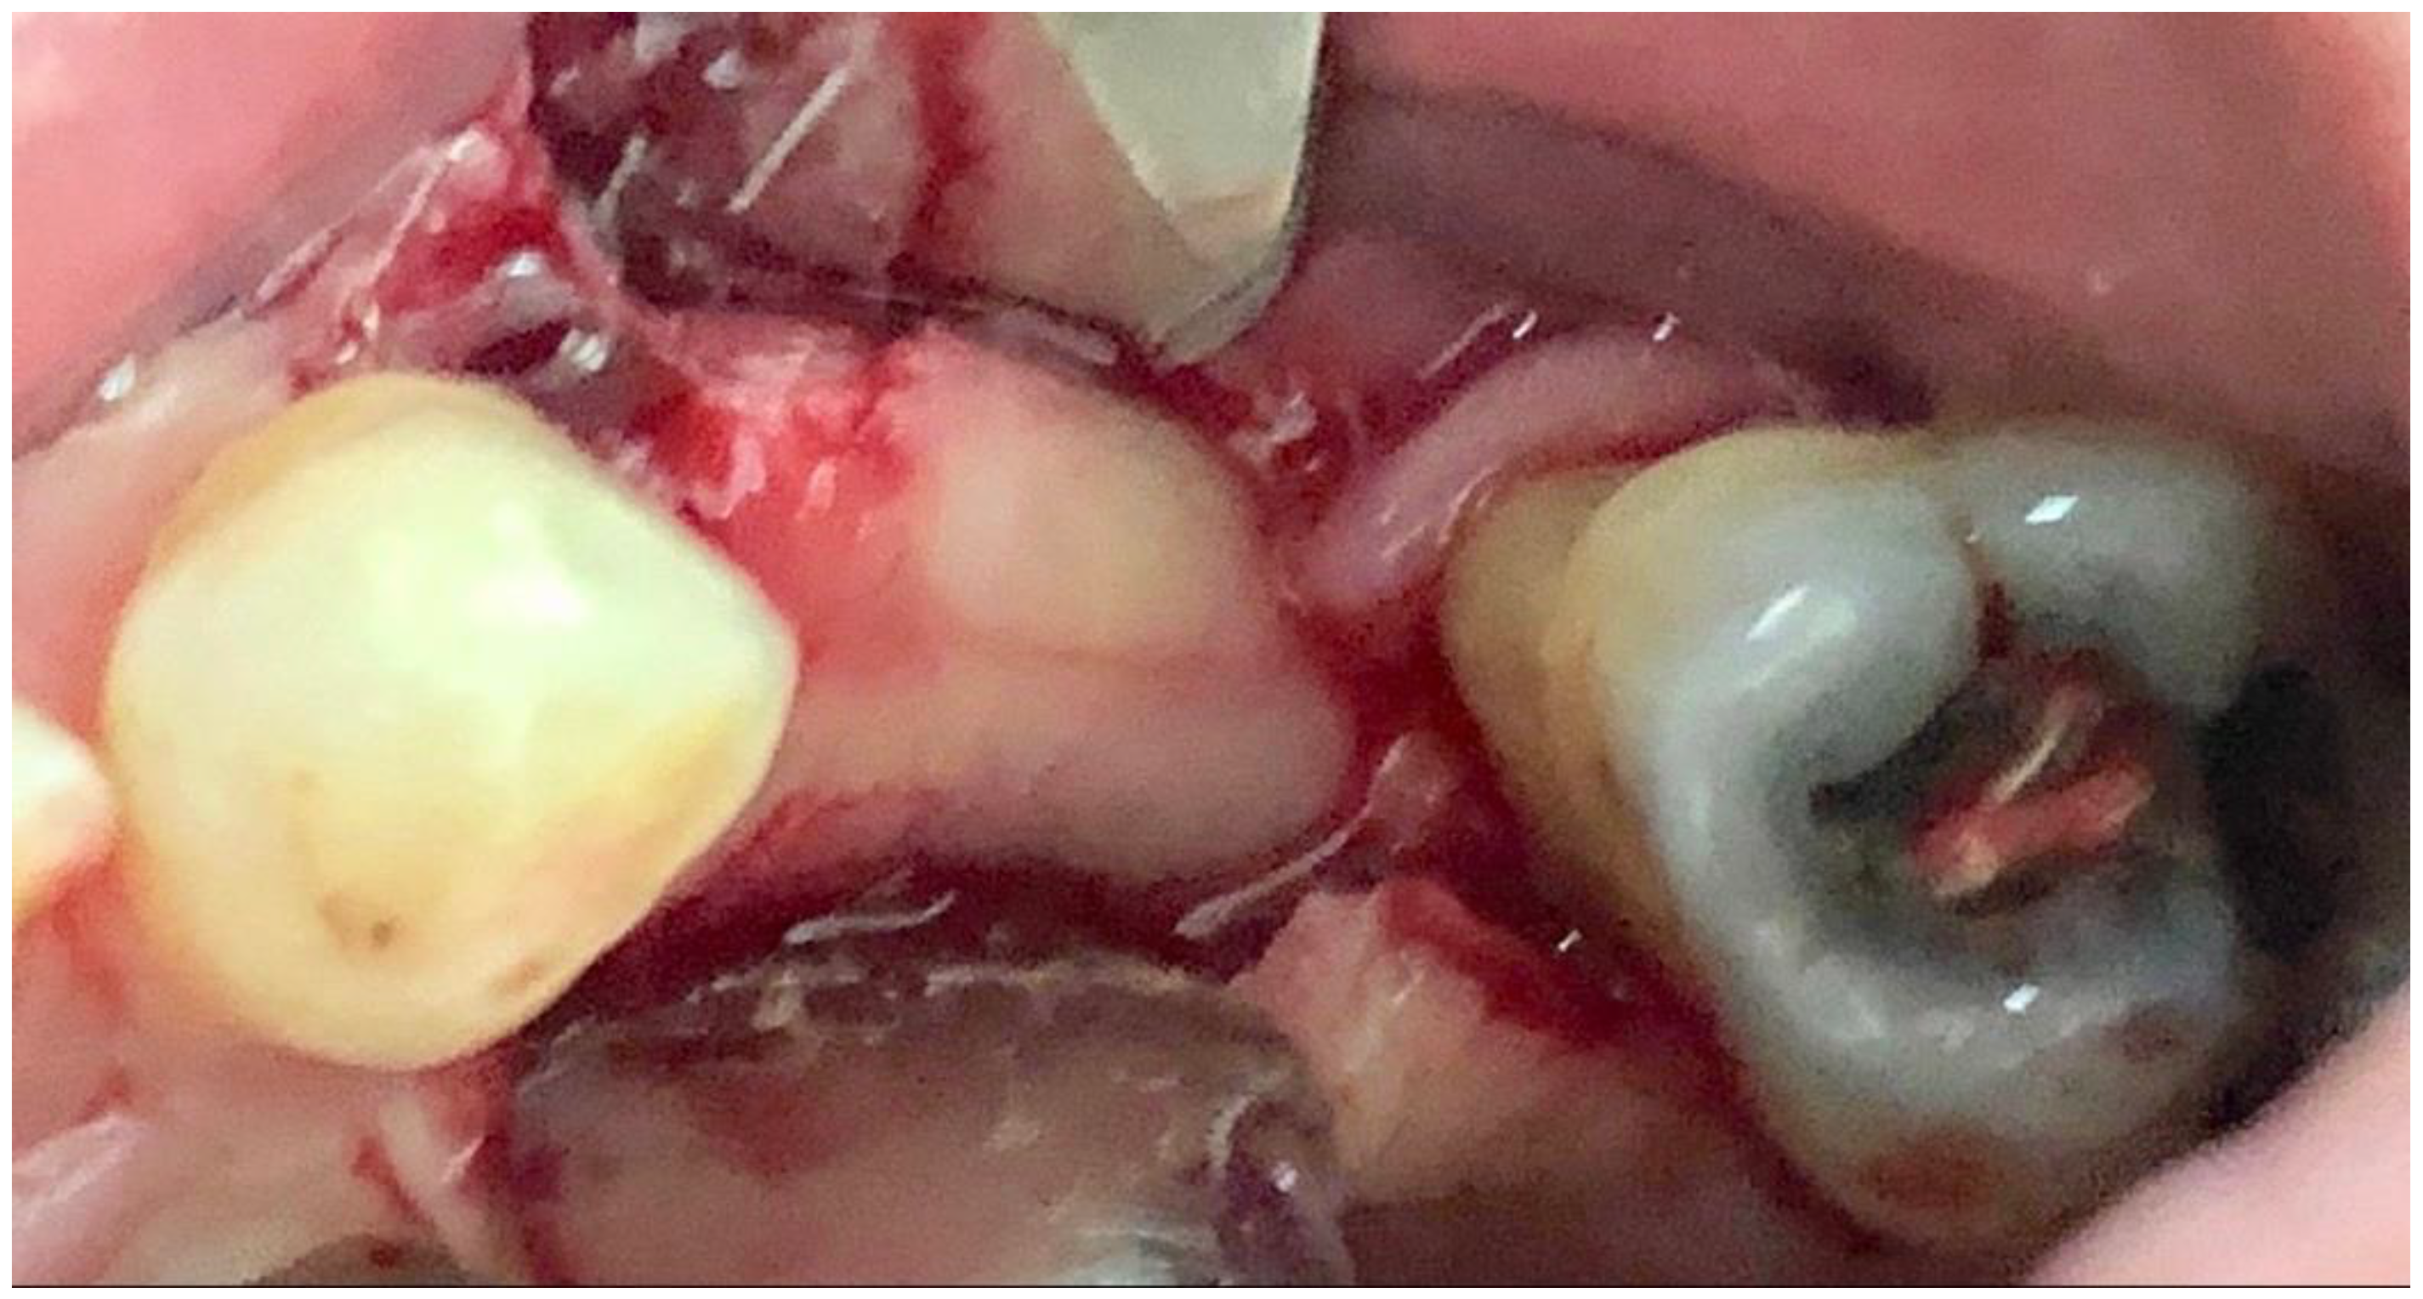

The bone lamina was shaped as a saddle, fixed to the buccal bone with two pins, and then, after the area was grafted with a mix of autogenous bone and collagenated xenograft (50–50%), reflected and stabilized under the palatal flap (Figure 7). Flaps were secured with 4.0 resorbable sutures and healing was uneventful.

Figure 7.

Bone lamina in place, arrows indicate the thickness of the lamina (1 mm) inducing both GBR and GTR effect.

Six months after surgery the area looked really different from the clinical and radiographic point of view; soft tissue sits near the CEJ of the teeth and a buccal bulk is restored. (Figure 8 and Figure 9).

Figure 8.

At 6 months both the hard and soft tissue augmentation is evident.